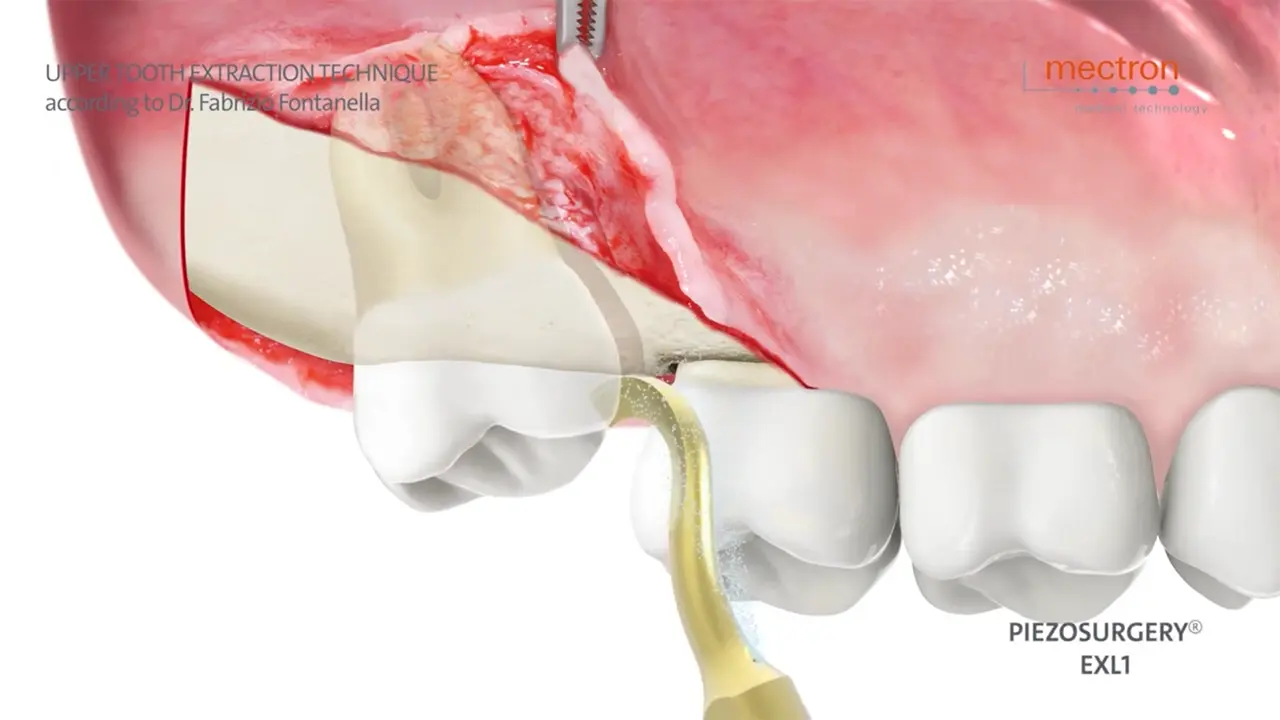

Upper tooth extraction

Dr. Fabrizio Fontanella